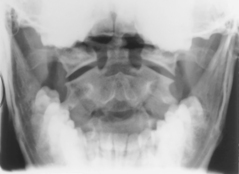

AP open mouth and AP (PA) dens critique